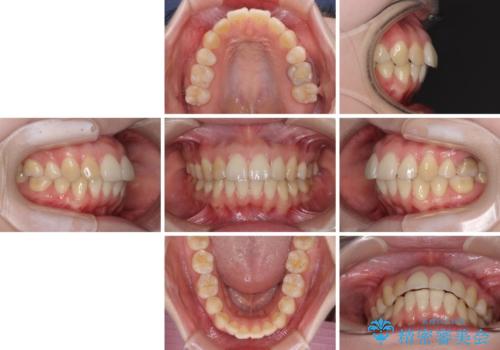

- 高校生の時に矯正治療を行ったものの、後取りをしてしまったとのことで来院された患者様です。

マウスピースでもワイヤー矯正でも対応可能でしたが、再度ワイヤーは装着したくないとのことでインビザラインにて矯正治療を行うこととしました。

インビザラインは長時間装着するための自己管理が極めて重要であり、自信はあまりないとのことでしたが、インビザラインを選択されました。

舌の突出癖が原因で後戻りをしたため、舌のトレーニングをしっかりと行っていただき、口元の突出感を改善することができました。

インビザラインの装着時間が守れず、1年強で終わる予定でしたが、4年間を要することとなりました。